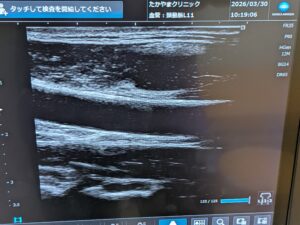

当院放射線科の特徴は、単純XP撮影での撮影・骨密度検査・超音波検査(エコー)などの画像診断を担当しています。撮影・検査後の画像や読影診断レポートを電子カルテと共有し、迅速な治療方針の決定に大きく貢献しています。骨密度検査は精度の高い骨密度測定器を導入しています。また、超音波検査(エコー)は、頸動脈(動脈硬化)・甲状腺・腹部等の検査を行っています。検査をご希望の方は、お電話でご連絡いただくか、お気軽にスタッフにお尋ねください。